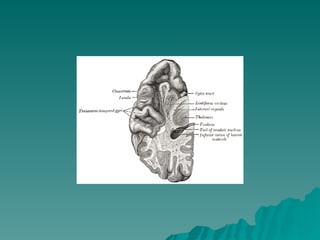

DISPOSIÇÃO  ANATÕMICA Núcleo Caudado  = Massa volumosa e alongada, relacionada  em toda sua extensão com os ventrículos laterais Cabeça  Corno Anterior Corpo  Assoalho Central Cauda  Extremidade Anterior do corno inferior A cabeça do núcleo caudado se funde com a parte anterior do núcleo lentiforme

DISPOSIÇÃO ANATÕMICANúcleo Caudado = Massa volumosa e alongada, relacionada em toda sua extensão com os ventrículos laterais Cabeça Corno Anterior Corpo Assoalho Central Cauda Extremidade Anterior do corno inferior A cabeça do núcleo caudado se funde com a parte anterior do núcleo lentiforme

LENTIFORME = FORMA DE UMA CASTANHA DO PARÁ Não aparece na superfície ventricular – Profundo Medialmente se relaciona com a cápsula interna  Separa do caudado e do tálamo Lateralmente  córtex da ínsula, separado pela  substância branca e pelo claustrum DIVIDIDO – Putamem = lâmina medial Globo pálido = lâmina mais lateral e branca  Coloração mais clara = fibras mielínicas que a atravessam PARTE EXTERNA GLOBO PÁLIDO  lâmina medular  medial PARTE INTERNA

LENTIFORME = FORMADE UMA CASTANHA DO PARÁ Não aparece na superfície ventricular – Profundo Medialmente se relaciona com a cápsula interna Separa do caudado e do tálamo Lateralmente córtex da ínsula, separado pela substância branca e pelo claustrum DIVIDIDO – Putamem = lâmina medial Globo pálido = lâmina mais lateral e branca Coloração mais clara = fibras mielínicas que a atravessam PARTE EXTERNA GLOBO PÁLIDO lâmina medular medial PARTE INTERNA